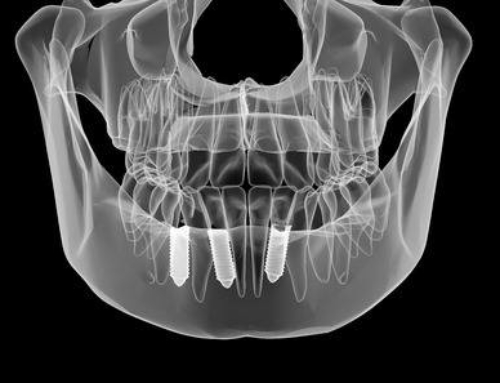

View Larger Image Dental Implantsunrise dentallab2018-09-17T05:56:30+00:00 Project Description Project Details Categories: Implants Share This Post FacebookTwitterLinkedIn Related Projects X-ray Finish